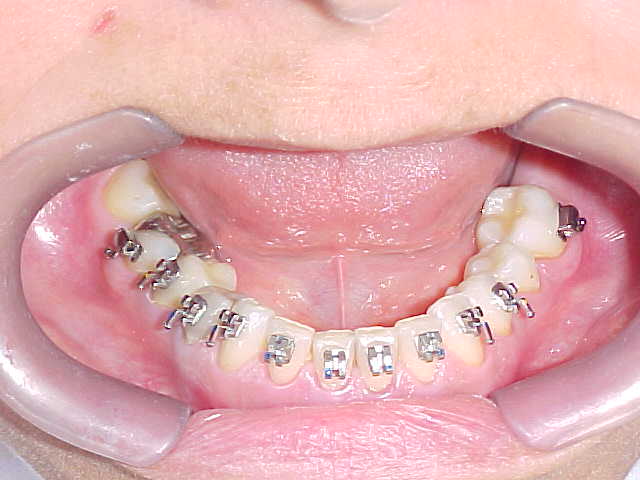

Aparelho ortodôntico instalado

Confirmação da inclinação lingual generalizada em todos os elementos dentários